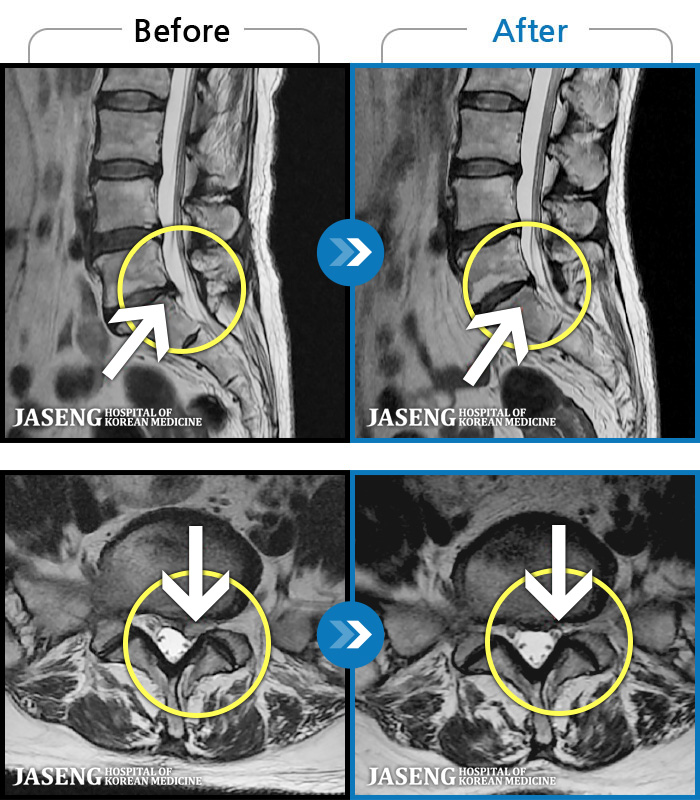

허리디스크

대전 · 김창연 원장

허리통증이라 왼쪽 발목~발등이 저려요. 엄지발가락에 힘빠지는 느낌, 전기오는 느낌이 있어요.

촬영시기

2023.07.17 ~ 2024.07.26

2024.08.09

조회수 521